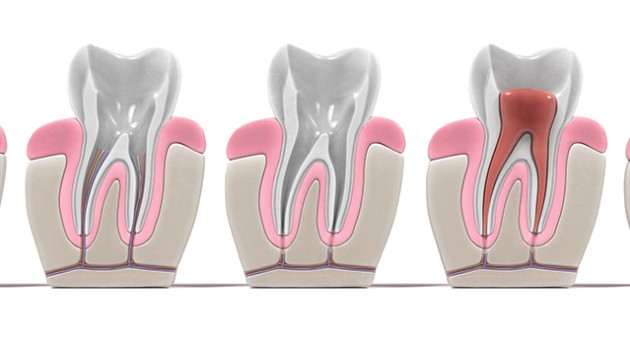

Lors d’une rage de dents, la cavité interne de la dent qui contient la pulpe est sous pression à cause d’une inflammation. En effet, cette partie de la dent n’est pas extensible. S’il y a une inflammation, cette dernière accroît la pression intérieure de la dent, ce qui provoque une intense douleur ou une nécrose de la pulpe dentaire.

Dans le cas où une carie atteindrait la pulpe dentaire, la dent doit être retirée et remplacée. Le protocole appliqué est celui de la dévitalisation, également appelé endodontie. Cet acte médical est généralement suivi par la pose d’une couronne.

Afin de poser une couronne dentaire, il est nécessaire de procéder à la dévitalisation de la dent. Ce processus se déroule en plusieurs étapes :

- Le débridement des débris d’amalgame ou le descellement des tenons pour accéder à la pulpe ;

- L’extraction de la pulpe dentaire ;

- Le remplacement de la pulpe par la gutta-percha, une gomme inerte.